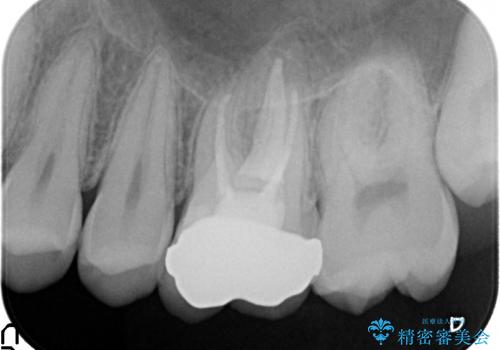

検査の結果左上6に持続痛を認めたため根管治療を行い、症状の緩解を確認後オールセラミッククラウンによる補綴を行いました。

- オールセラミッククラウン…¥100,000、ファイバーコア…¥20,000、仮歯…¥10,000費用は治療当時の料金となります

今回用いたオールセラミッククラウンはジルコニアフレームという白い素材の上にセラミックを盛っているため、審美性が非常に高いのが特徴です。

また、ジルコニアは人工ダイヤモンドの材料にも使われているほど高い強度を持っており、そのためオールセラミッククラウンは審美性だけでなく、奥歯やブリッジの補綴も可能とするクラウンです。